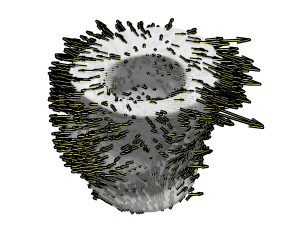

Fig. 5 demonstrates a 3D visualisation of the 3D velocity field from a full stack of TPM at peak expansion (a) before translational motion compensation, (c) after before translational motion compensation with method 1 and (b) method 2. The 3D visualisation of the uncorrected stack shows a bias in the velocity field caused by translational velocity, whereas the corrected stacks look more balanced. This visualisation of results pictures the difference in the two methods: Method 1 yields a stack which looks overall more symmetric as correction has been applied slice by slice taking into account the centre of mass per slice. On the other hand method 2 yields a stack where the base seems to move in opposite direction to the mid-wall and apex, revealing a relative motion between the lower and upper part of the LV. Visualisation of the second stack is looks more realistic and method 2 is recommended when examining deformation from the entire volume. When looking at deformation slice by slice method 1 yields more intuitive results and it is recommended in that case.